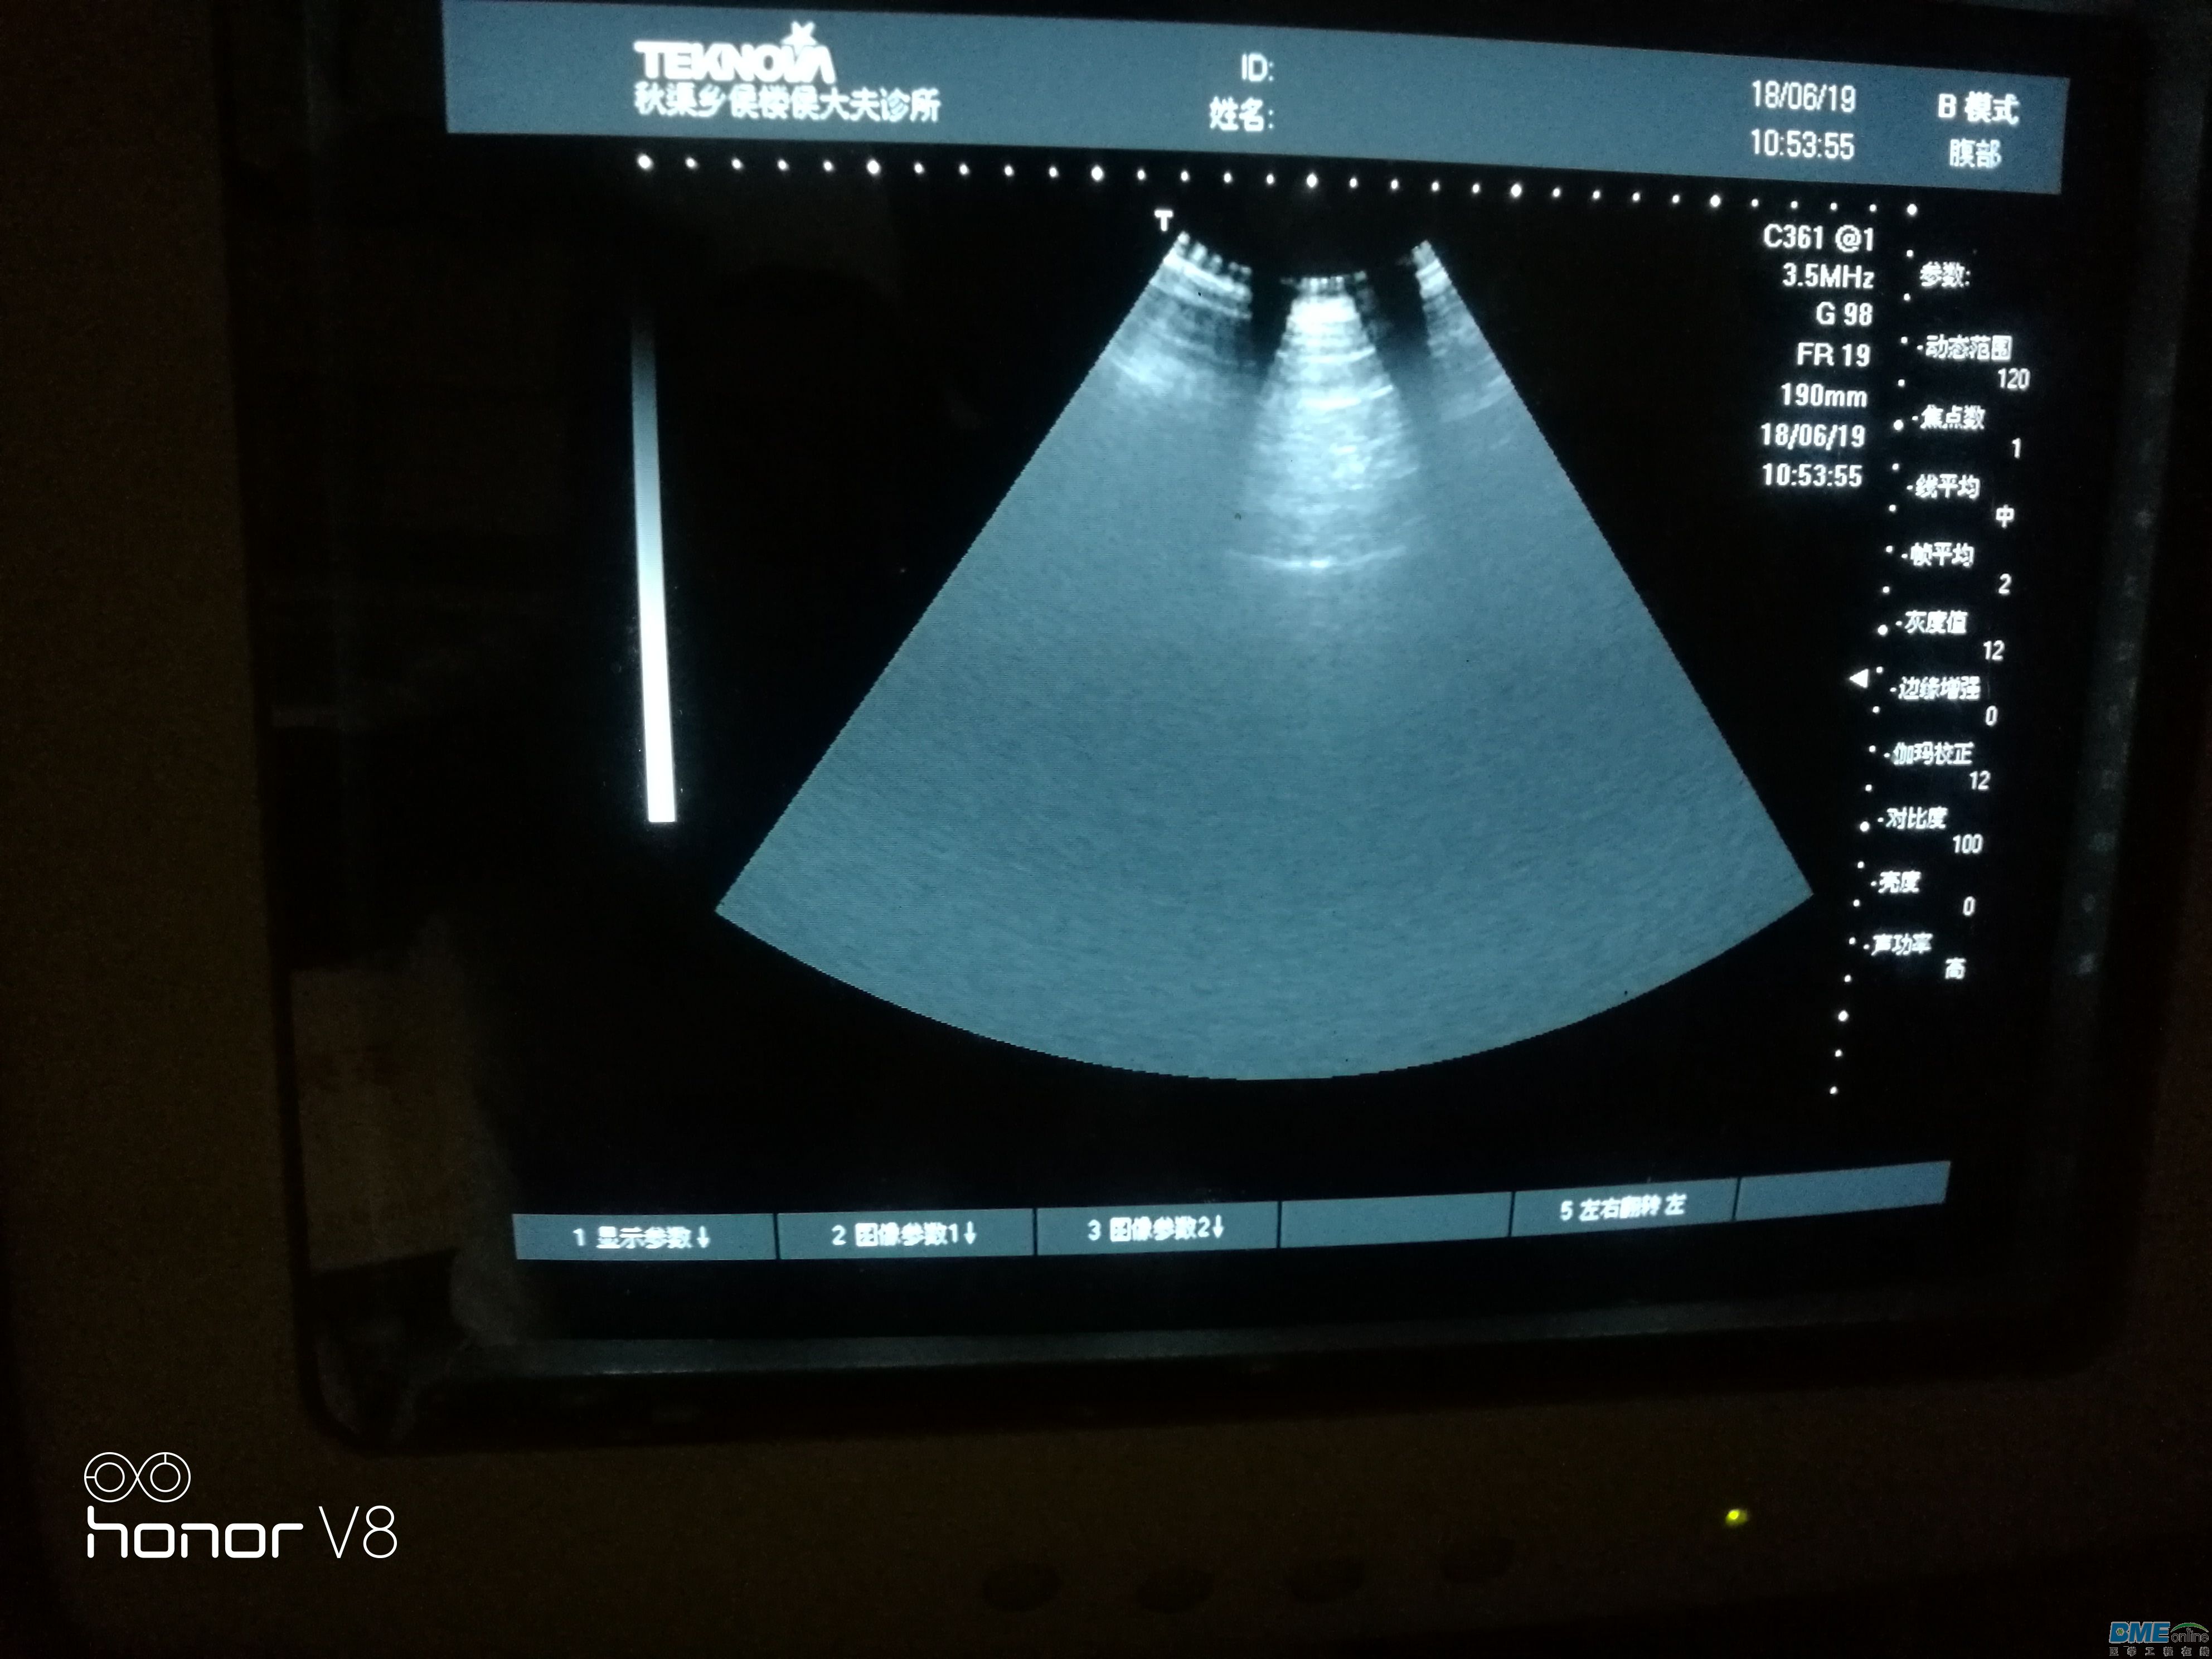

今天接收一台天惠华TH-200的B超级,问题是扇形区域里图像变小,如图扇形区域里只有上部分有图像,拔下探头图像不变。

,下面图是接入探头后直接测试腹部的图片,图上可以看出隐隐约约的影像探头接入后探测腹部扇形区域能有阴影的影像,开机拔去探头扇形区域只有一点点影像!求教维修思路